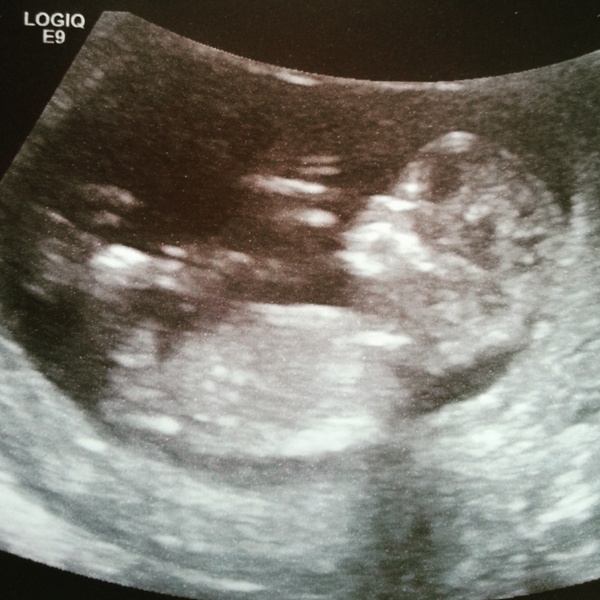

TwoBeesInTheHive · 12/05/2015 13:55

Here's my little Bee! Dixiebell you will be pleased to hear, there was only one and they only put my dates forwards a few days, so must be third baby syndrome!! Grin also my due date is now the 19th so can someone bump me up the list please? Thankyouuu Grin